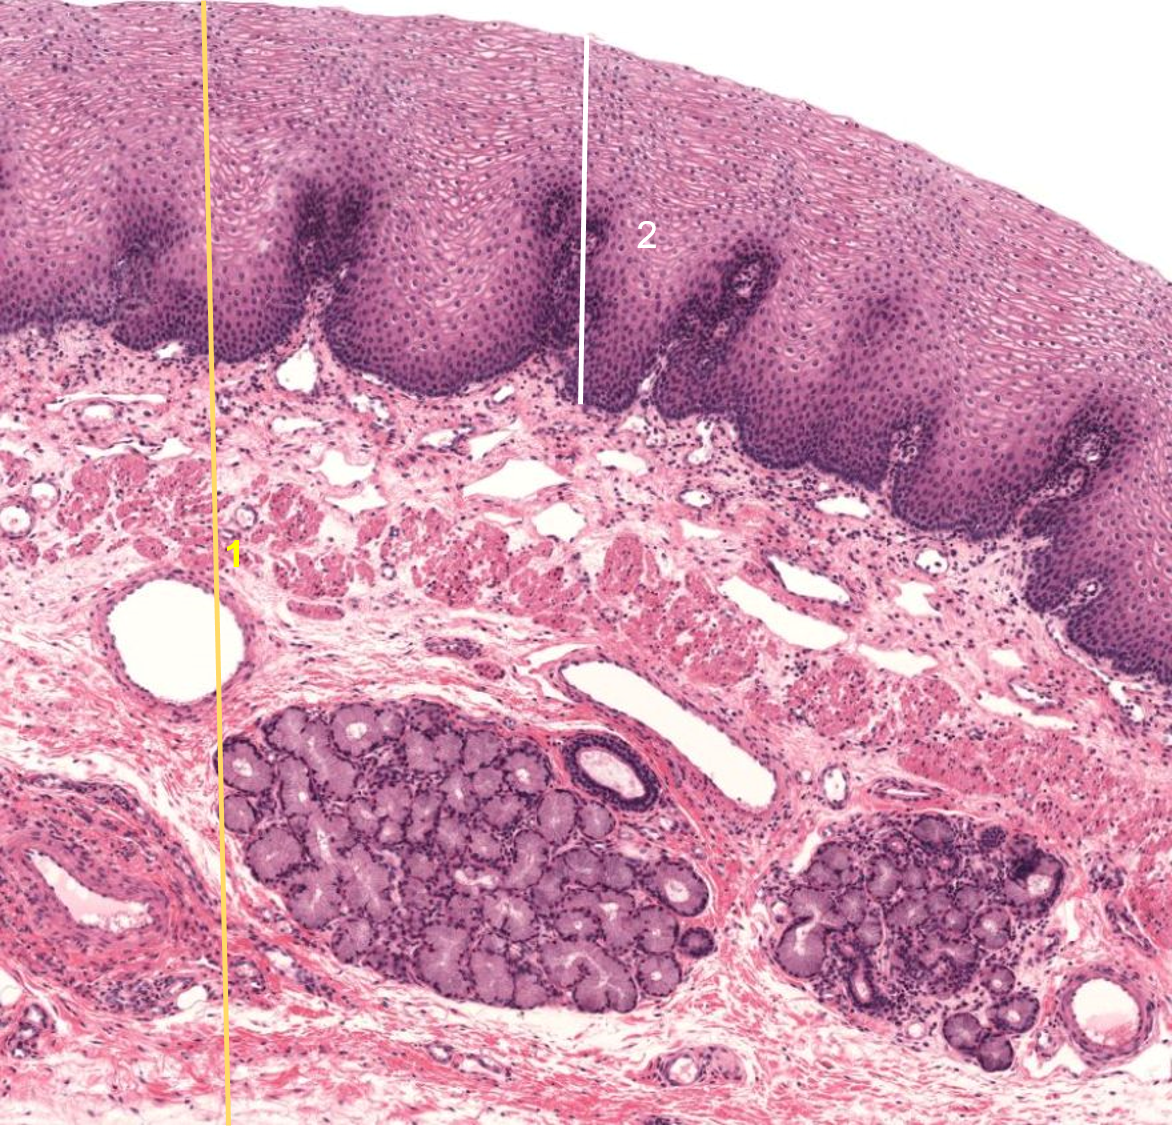

1: Esófago

2: Epitélio pavimentos estratificado não queratinizado

1: Língua

2: Papila circunvalada

1: Língua

2: Papila filiforme

3: Músculo esquelético